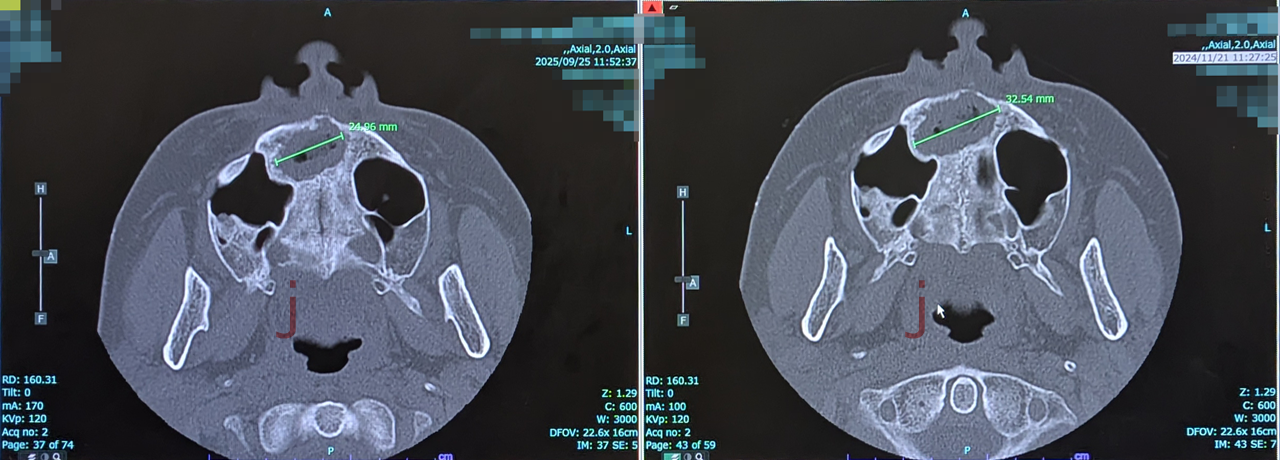

CT画像による嚢胞サイズ縮小の確認

上のCT画像では、右が2024年11月に撮影したもの、左が2025年9月に撮影したものです(※左右は病院提供の画像順に合わせています)。

そして、2024年11月の再撮影時点では嚢胞は約3.25cmに縮小。この時点で、当初あった前歯のぐらつきは完全になくなっていました。

さらに、2025年9月に再度CTを撮影したところ、嚢胞は約2.5cmまで縮小していました。

2024年11月から2025年9月までの10ヶ月間で、嚢胞の大きさは約23%減少し、当初のサイズの約77%にまで縮小した計算になります。